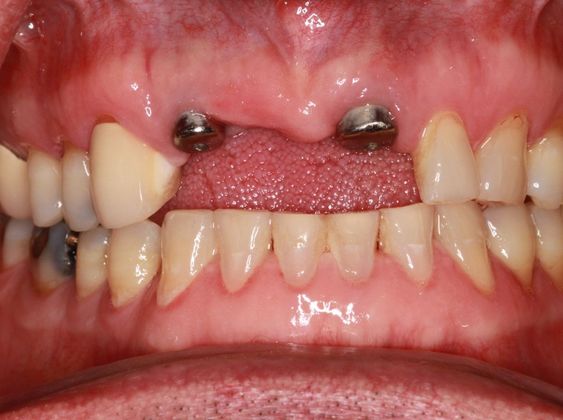

Dental Implants: Case 8

This patient presented after years of wearing a removable partial denture. The patient lost his front teeth from a traumatic event and now wanted a more permanent restoration. Two dental implants were placed and an implant bridge was made in the area. It was decided that two implants would be better than three and would give a more aesthetic result. The patient was very pleased with the final outcome and even more pleased to not have the extra expense of another dental implant.